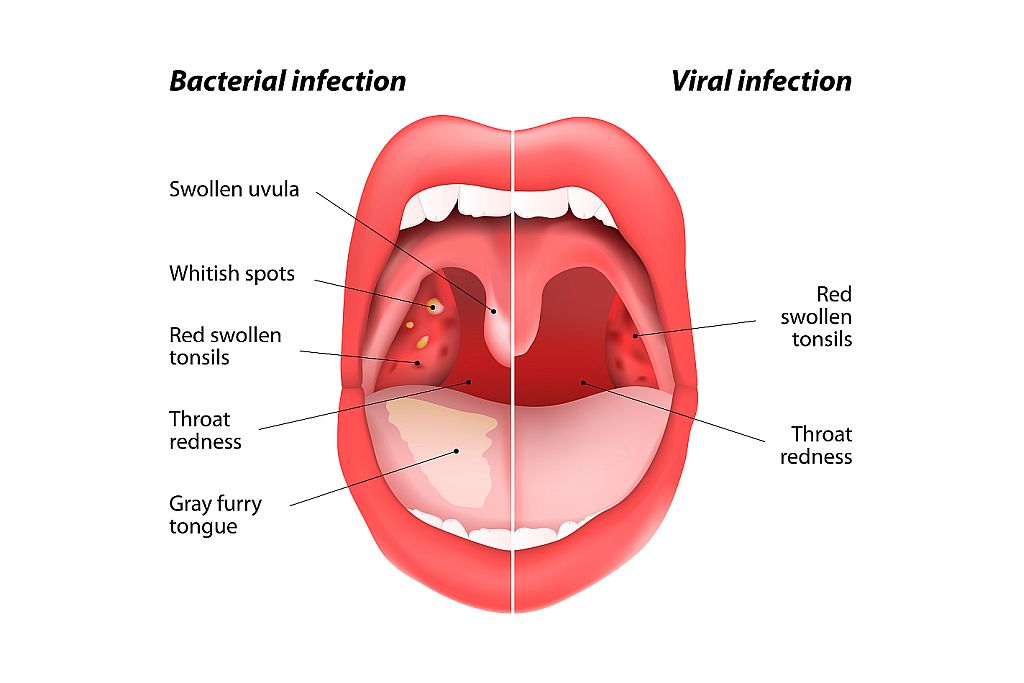

Клиническое течение при ангине у каждого ребенка может отличаться, учитывая тип заболевания:

- Катаральная, которая является наиболее распространенной и протекает легче, чем другие типы болезни. Проявляется поверхностным поражением миндалин с появлением небольших красных участков на слизистой оболочке. Симптоматика выражена не остро, при этом возможно незначительное повышение температуры до 37-38°С. Ребенку часто ставится такой диагноз при развитии заболеваний верхних дыхательных путей.

- Фолликулярная или гнойная. Отличается более острым течением, часто сопровождается высокой температурой – 38°С и выше. При подобной форме на миндалинах можно обнаружить небольшие белые или желтые гнойники не больше 2 мм. При гнойной ангине увеличиваются и болят при пальпации лимфоузлы на шее и затылочной части.

Проявиться разные виды заболевания могут при воздействии на небные миндалины патогенных микроорганизмов – вирусов, бактерий, грибков. У детей младшего возраста ангина преимущественно имеет вирусное происхождение, проявляясь вследствие вируса герпеса, Эпштейн-Барра, аденовируса, цитомегаловируса. У школьников заболевание возникает при воздействии стрептококков, стафилококков, грибков, спирохет, пневмококков. Здоровый детский организм способен противостоять воздействию инфекции. Заболевание развивается при ослаблении иммунной системы на фоне переохлаждения, усиленных физических нагрузок, частых стрессов, несбалансированного питания, рецидивирующих респираторных заболеваний.

Причины бактериальной ангины у детей

Бактериальная ангина представляет собой инфекционное заболевание, при котором возникает воспаление ткани небных миндалин в результате попадания на них патогенных микроорганизмов, либо увеличения числа условно-патогенных микроорганизмов. Они проникают воздушно-капельным путем от инфицированного человека к здоровому при кашле, чихании, при использовании одних и тех же столовых приборов, полотенец и др.

Наиболее часто бактериальная или гнойная ангина у детей вызывается бета-гемолитическим стрептококком группы А. Причина заключается, прежде всего, в его строении: они несут капсулы (М-белок) для адгезии к слизистой оболочке миндалин. Эти микроорганизмы устойчивы к фагоцитозу и выделяют различные экзотоксины. Последние приводят к выработке антител, которые перекрестно действуют еще и на сердечную мышцу, ткань сосудов, суставов и почечную паренхиму.

По степени воспаленности миндалин, ангина у детей может иметь несколько видов:

- катаральная. При осмотре зева видно, что небные дужки, миндалины увеличены и покрыты серозным белесоватым налетом;

- фолликулярная. Характерным признаком является наличие гнойных точек на миндалинах, размер которых может быть до трех миллиметров;

- лакунарная. Осмотр зева, открывает отекшие и сильно покрасневшие миндалины, покрытые налетом гноя, желтого цвета;